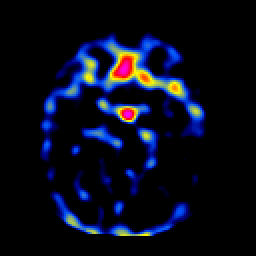

SPECT TL Study #1 -- Slice #20

[Home][Help][Clinical][Tour 1][Tour 2][Tour 3] Slice 20